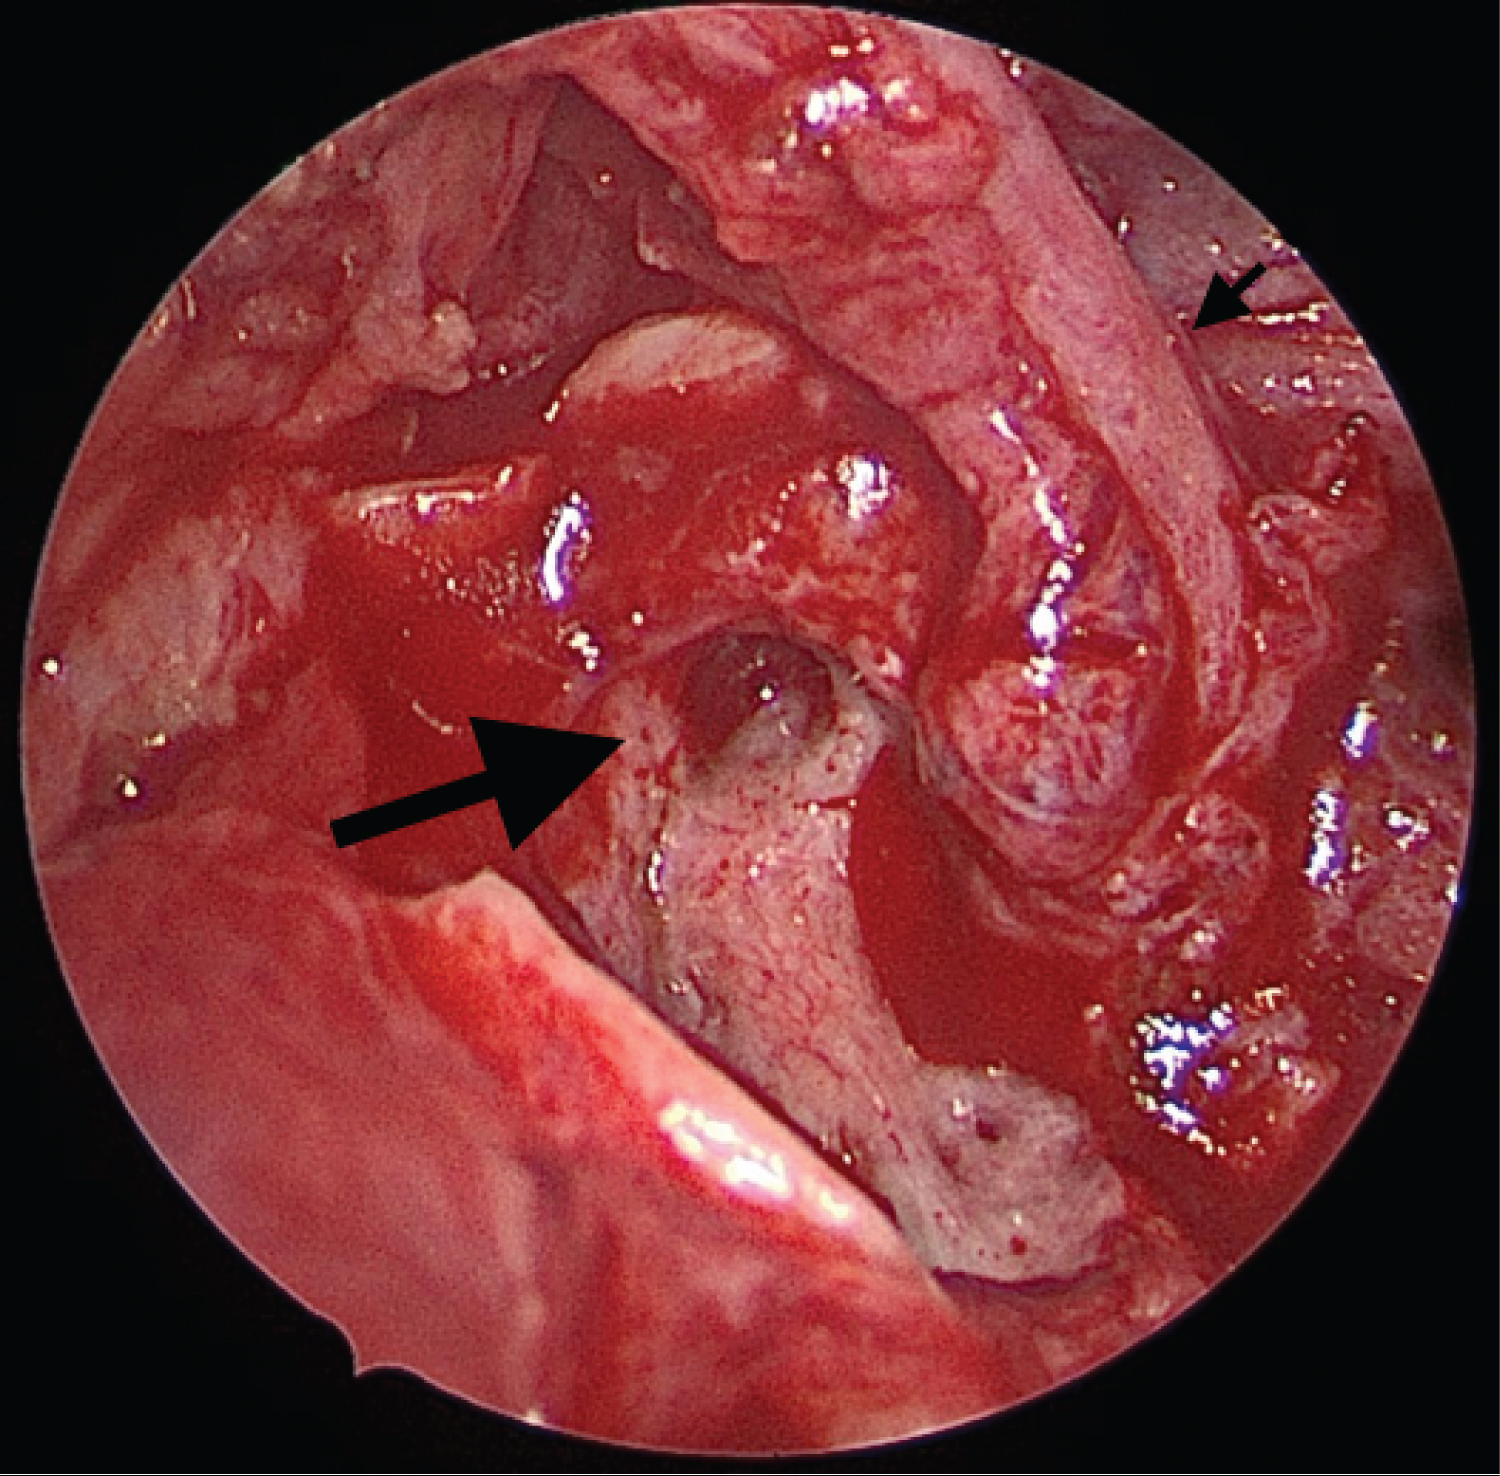

Under general anesthesia, a Blair incision was made to access the parotid mass, the root of the facial nerve was located. A well circumscribed cystic mass was identified at the tail of the parotid and extended medially and deep to the inferior division of the facial nerve (Figure 3). At the superior most extent of the mass, just deep to the main trunk of the facial nerve, the mass was connected to a cartilaginous stalk that appeared to be a duplicate EAC. The cyst itself was freed from the surrounding soft tissue, and as dissection was carried superiorly along the cartilaginous stalk it was found to be intertwined with the facial nerve. Once the proximal cartilaginous tract was dissected away from the nerve and excised, a STORZ rigid endoscope was used to examine the tract and a second, cartilaginous lumen was discovered which ended in a blind pouch proximally, with the facial nerve coming across it (Figure 4). Once the cyst and cartilaginous stalk were removed, the endoscope was re-introduced to confirm there was no communication or involvement of the EAC, and it was determined that the second lumen was too close to the facial nerve to safely resect. Prior to closure of the wound, the facial nerve was stimulated and was functional. Surgical pathology and cytology confirmed a type II first branchial cleft cyst. Post-operatively the incision was healing well, the facial nerve was intact, and the patient was pleased with the cosmetic appearance.

Figure 4: Cartilaginous portion of the branchial cleft cyst with close association of facial nerve. Small arrow: Root of the facial nerve; Large arrow: Cartilaginous portion of the branchial cleft cyst running deep to the facial nerve. View Figure 4